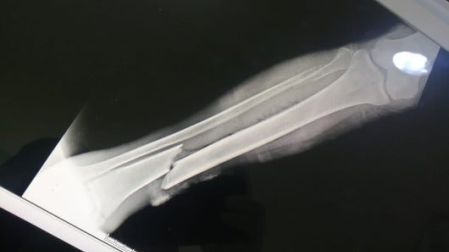

Paramédicos del municipio de Chalco en el Estado de México (Edomex), peregrinaron este martes durante 17 horas por diferentes hospitales con un señor indigente de 57 años que fue atropellado y tenía una fractura expuesta en el pie derecho.

Con este paciente estoy desde las 7 de la mañana, fui al hospital General de Valle de Chalco y me argumentaba el ortopedista que no tenía espacio físico y que el tiempo que él tenía era hasta septiembre, fui al hospital de alta especialidad, solamente le pusieron una férula, le hicieron un lavado mecánico, lo suturaron y nos dijeron que no tenían presupuesto para el material que él necesita por lo que no te lo puedo recibir” dijo el paramédico al ser entrevistado por Grupo Imagen.

El señor dijo que confía en las manos y la voluntad de los doctores y espera que actúen con profesionalismo para su recuperación, pues teme que por su situación puedan tomar decisión de amputarle el pie en vez de ayudarlo a recuperarse.